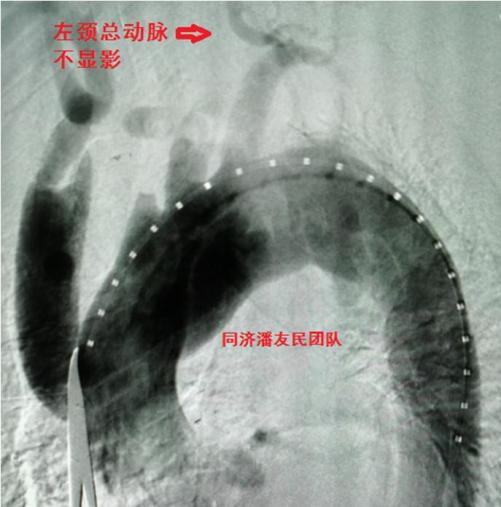

平稳度过保守治疗期,我们设计了杂交手术的方式,从升主动脉接人工血管到头臂干动脉、左颈总动脉及左锁骨下动脉(去分支技术),同期行胸主动脉覆膜支架植入,覆盖主动脉弓上三大分支开口(图7、8)。

释放支架后再次主动脉造影,发现杂交手术重建的左颈总动脉血流仍不通畅,尝试取栓未成功,考虑远端血管堵塞(图9)。